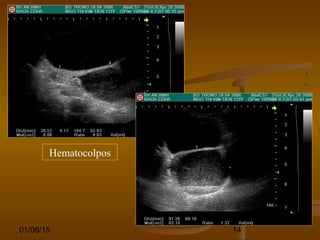

Hematocolpos